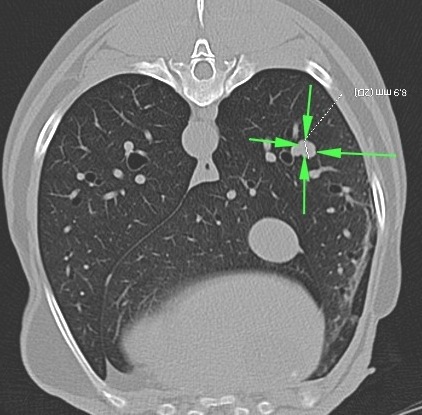

Fig 2a and 2b: Transverse and Coronal CT reconstructions of the same mass shown in figure 1.

Fig 3: Same case as figures 1-2: A second small (9mm) mass adjacent to a blood vessel is seen within a separate lung lobe. This nodule was not visible on screening radiographs. Other grey “spots” are branching blood vessels